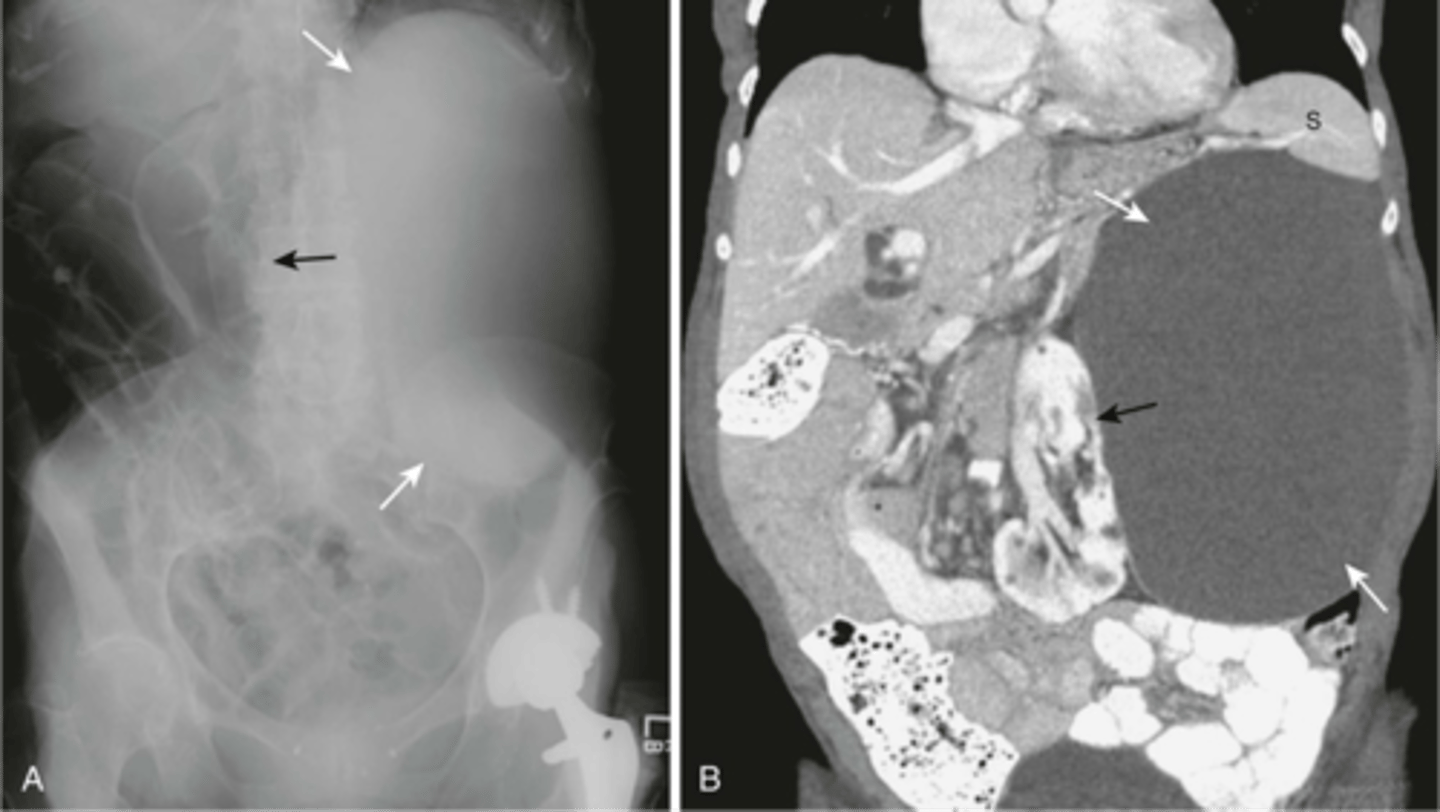

Abdominal aortic aneurysm on CT